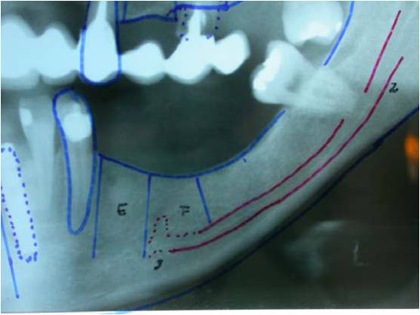

Radiograficamente, além do planejamento para os implantes, são avaliados todo o trajeto do nervo alveolar e a posição do forame mentoniano, utilizando-se da ortopantomografia, ou ainda de tomografia computadorizada (16).

Pode-se com isso fazer um traçado predicativo do local das osteotomias e, na tomografia, avaliar densidade do osso medular, a espessura das corticais e, as medidas precisas da posição do canal mandibular em todo seu trajeto

Fig. 1 - Radiografia ortopantomográfica mostrando o traçado do canal do nervo alveolar inferior.

Estudo radiográfico perfeito para a concretização da manobra cirúrgica, levando-se em consideração todos os detalhes da localização do plexo alveolar inferior e suas relações anatômicas (Figs. 2 e 3).

Figs. 2 e 3 – Aspecto radiográfico mostrando a perfeita localização do plexo alveolar inferior com as medidas corretas para a manobra cirúrgica com a localização do implante.